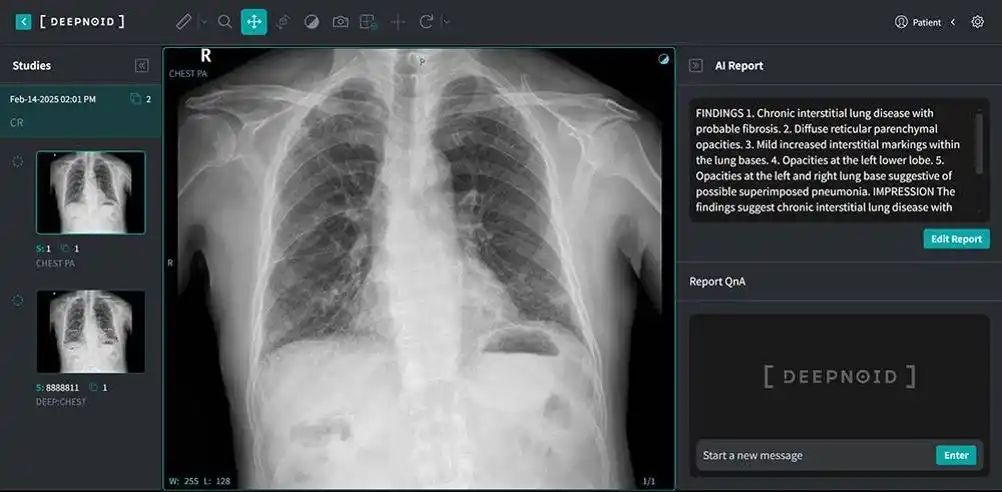

「M4CXR、胸部X線をAI解析し所見書ドラフトを生成するソリューション」

インタビューに先立ち、DEEPNOIDのソリューション全体について説明を求めた。キム専務は「M4CXRは胸部X線データを基に読影所見書のドラフトを自動生成するソリューションだ。技術面では2015年からディープラーニング研究を進め、MRA(磁気共鳴血管造影)を用いた脳動脈瘤検出や、各種病理画像を通じた大腸がん、腎がん、胃がん分析・検出技術などを開発してきた」と説明した。

DEEPNOIDの胸部X線データ分析および読影所見書生成AI「M4CXR」。所見書生成にFuriosaAIのNPUが導入される予定だ / 出典=DEEPNOID

これを基に、AIベースの胸部X線診断支援ソリューション「DEEP:CHEST(ディープ:チェスト)」を開発し、現在はM4CXRへと機能を高度化している。加えて、脳MRA向けのDEEP:NEURO(ディープ:ニューロ)、肺疾患対応のDEEP:LUNG(ディープ:ラング)など医療AIサービスも展開している。中でもDEEP:NEUROは革新医療機器に指定され、非保険診療でも診療報酬が認められている点が特徴だ。産業用X線向けのSkymaru:Security(スカイマル:セキュリティ)、DEEP:Security(ディープ:セキュリティ)、DEEP:Factory(ディープ:ファクトリー)といったソリューションも手掛けている。

競合他社との差別化について、キム専務は「生成AIを用いて読影所見書のドラフトを作成する技術が中核だ。2023年から胸部X線向け生成AI技術に関する論文を書いている最中で、今年は臨床試験を終え、食品医薬品安全処のデジタル医療機器認可手続きを進めている。医療機器企業として生成AIを本格活用している点で、独自性の高い技術力を有している」と語った。肺疾患に特化しつつも、気管支、心臓、胸壁、骨、その他臓器まで総合的に評価できる点も強みだという。

ヒョン研究所長は「利用者から見るとM4CXRで胸部X線を解析し、所見書ドラフトが生成されるだけに見えるが、実際には暗号化・匿名化を経てデータを受信し、内部ソフトウェアで処理した後、X線で確認可能な多くの疾患について言語モデルが所見書として出力する」と説明した。